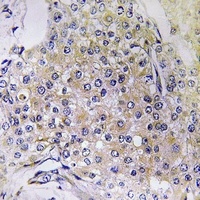

IHC analysis of NDUFS6 using anti-NDUFS6 antibody. NDUFS6 was detected in a paraffin-embedded section of human breast cancer tissue. Heat mediated antigen retrieval was performed in EDTA buffer (pH8.0, epitope retrieval solution). The tissue section was blocked with 10% goat serum. The tissue section was then incubated with 2 µg/ml rabbit anti-NDUFS6 Antibody overnight at 4°C. Peroxidase Conjugated Goat Anti-rabbit IgG was used as secondary antibody and incubated for 30 minutes at 37°C. The tissue section was developed using HRP Conjugated Rabbit IgG Super Vision Assay Kit with DAB as the chromogen.